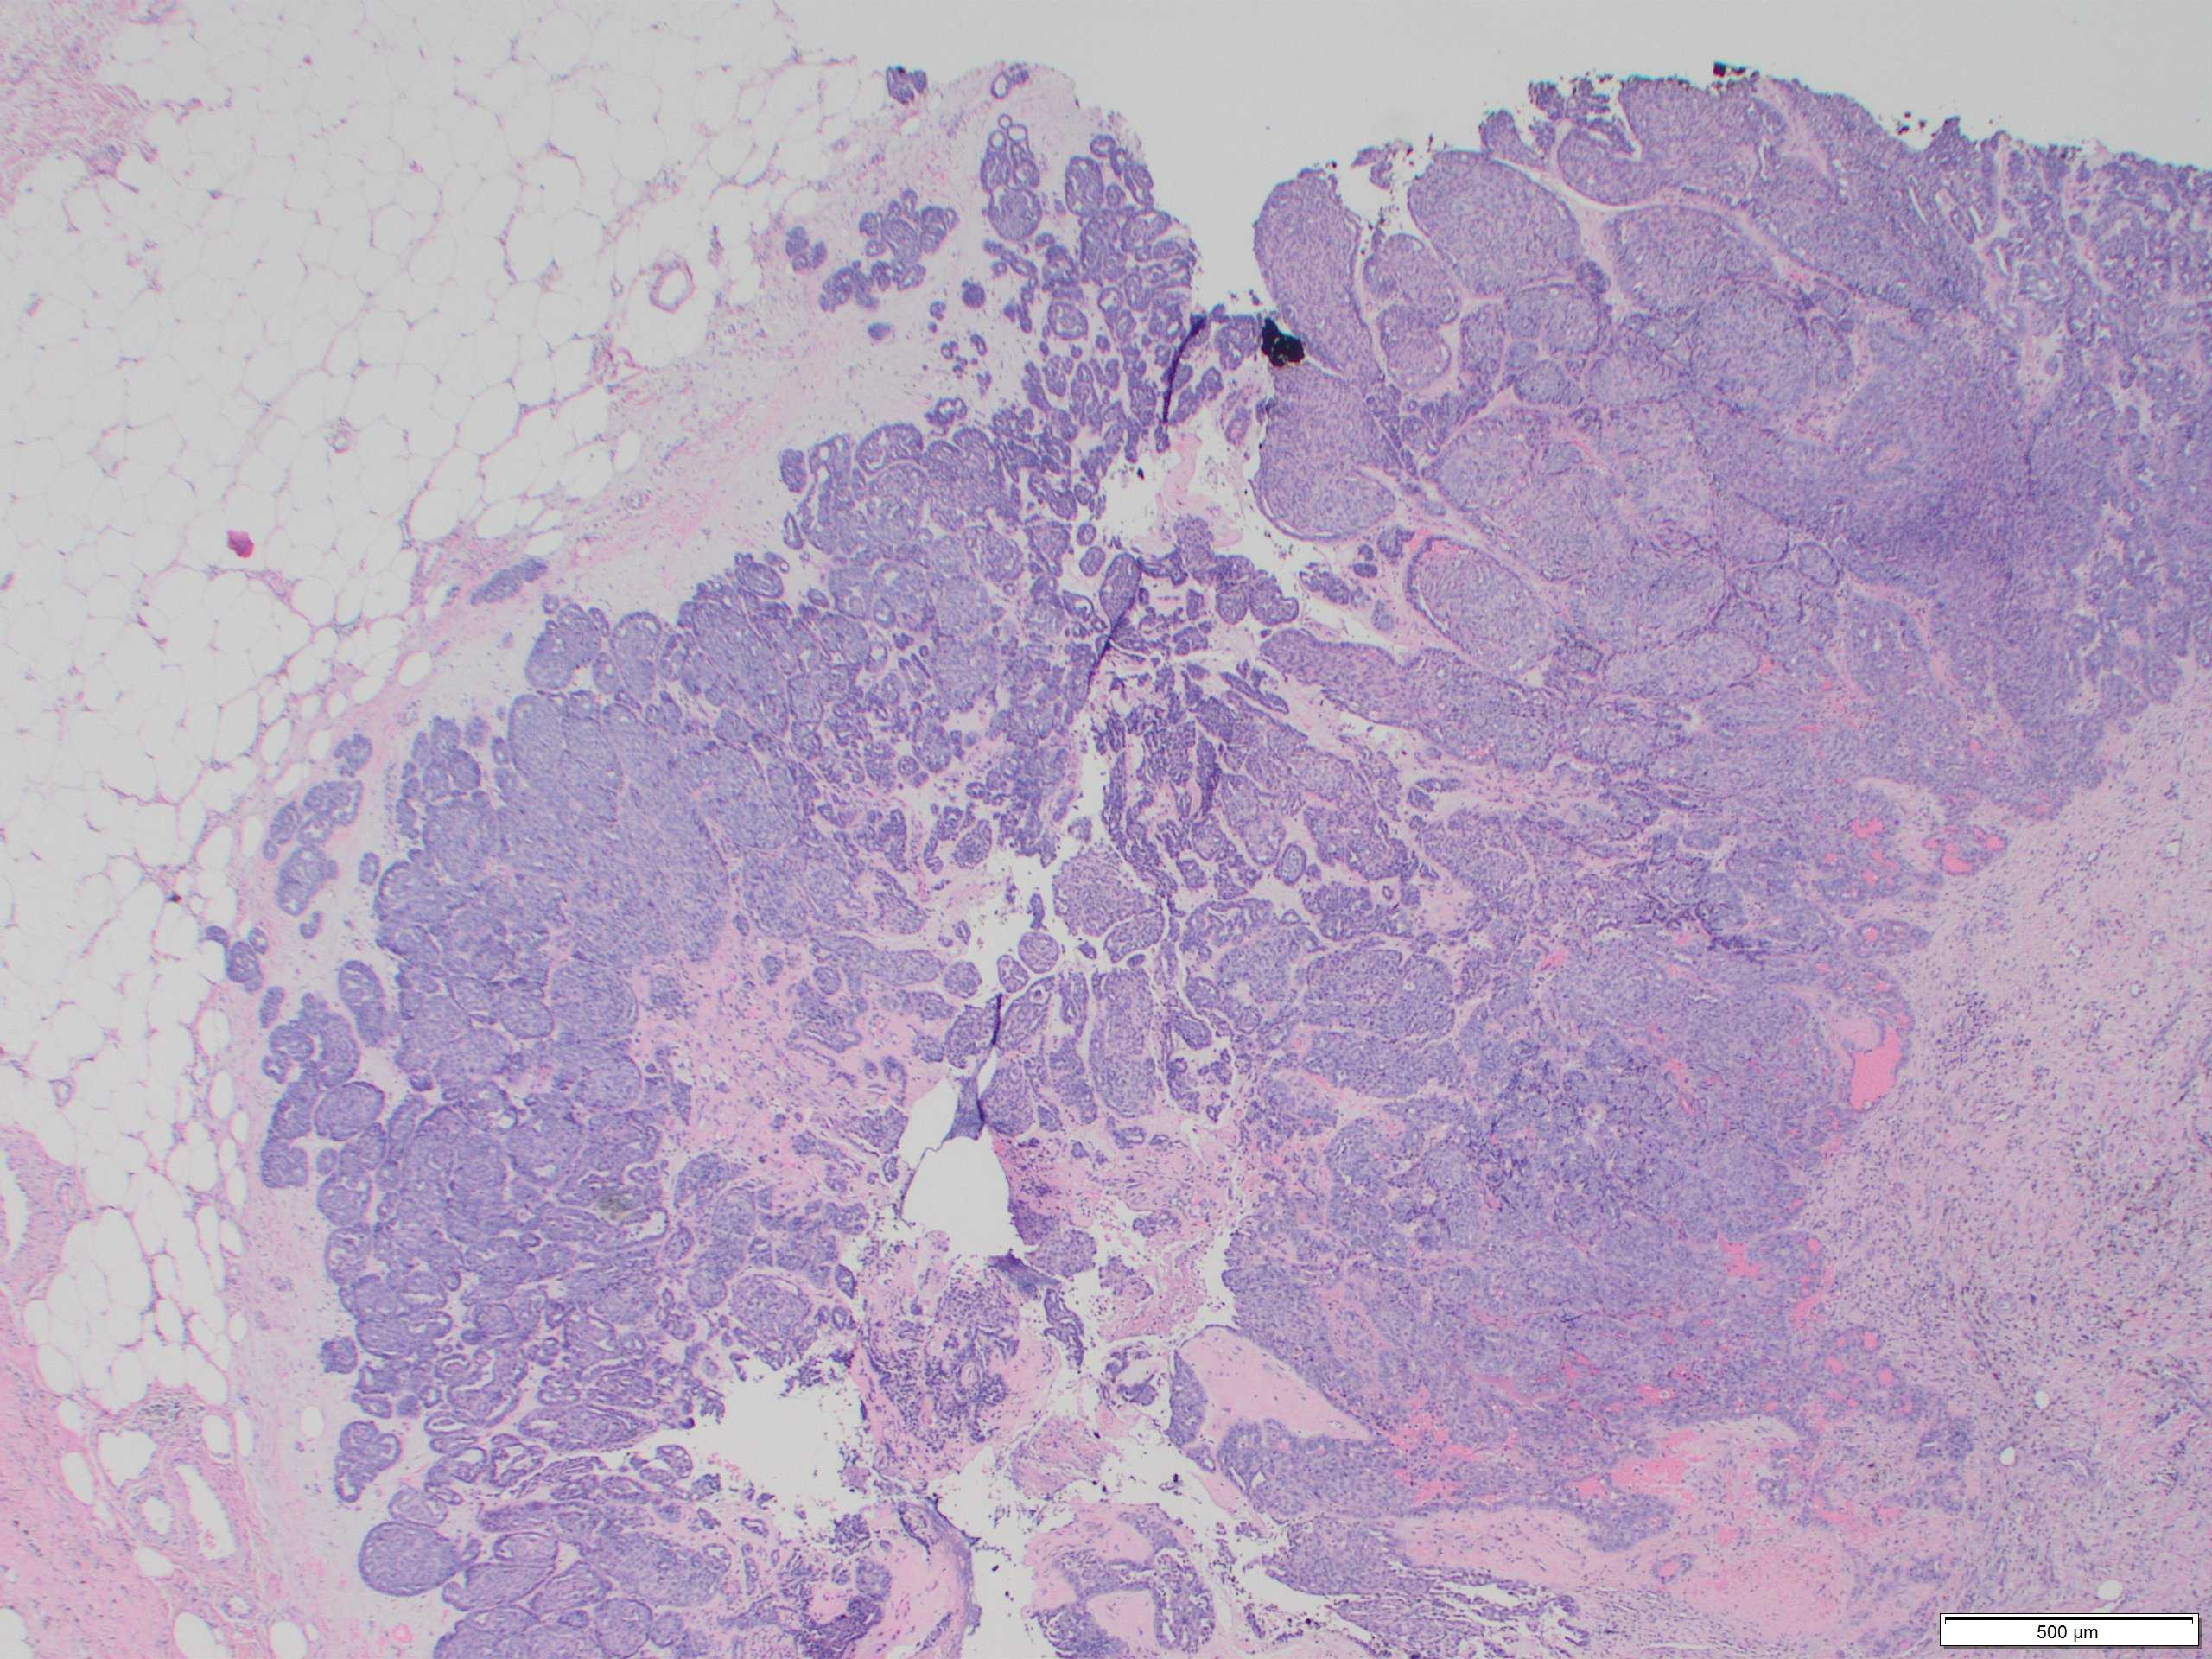

Classic AME is rare, accounting for less than 0.5% of breast tumours. It predominantly affects older women. Radiologically, AME forms a round or lobulated dense mass with margins that may be indistinct. Local recurrences have been reported in approximately 10%.

Malignant AME (M-AME) shows varied macroscopic appearances from a multilobulated, well-defined mass, similar to classic AME, to a poorly defined mass with infiltrative borders. Histological features of malignancy: overgrowth of the epithelial or myoepithelial component, mild to moderate cytological atypia, and increased mitotic activity with or without mildly infiltrative growth pattern, and/or focal necrosis.